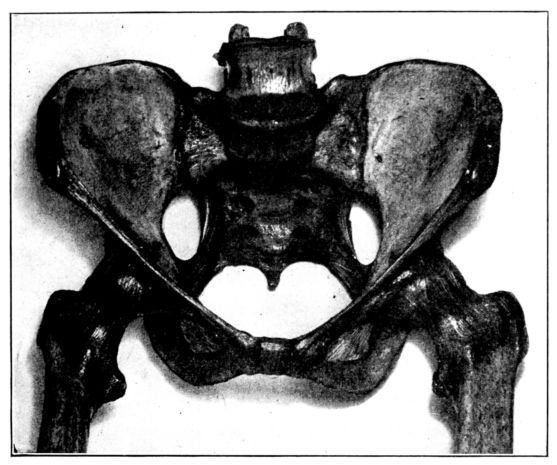

Viewed in its entirety, the pelvis is an irregularly constructed, two-storied, bony cavity, or canal, situated below and supporting the movable parts of the spinal column, and resting upon the femora or thigh bones. (Fig. 1, A. and B.).

Four bones enter into the construction of the pelvis: the two hip bones or ossa innominata, on the sides and in front with the sacrum and coccyx behind.

The innominate bones (ossa innominata), symmetrically placed on each side, are broad, flaring and scoop-shaped. Each bone consists of three main parts, which are separate bones in early life, but firmly welded together in adults: the ilium, ischium and pubis. The ilia are the broad, thin, plate-like sections above, 20their upper, anterior prominences, which may be felt as the hips, are the anterior superior spinous processes used in making pelvic measurements. The margins extending backward from these points are termed the iliac crests.

The ischii are below and it is upon their projections, known as the tuberosities, that the body rests when in the sitting position, and which also serve as landmarks in pelvimetry. The pubes form the front of the pelvic wall, the anterior rami uniting in the median line by means of heavy cartilage and forming the symphysis pubis.

The sacrum and coccyx behind are really the termination of the spinal column, the sacrum consisting, usually, of five rudimentary vertebrae which have fused into one bone. It sometimes consists of four bones, sometimes six, but more often of five. The sacrum completes the pelvic girdle behind by uniting on each side with the ossa innominata by means of strong cartilages, thus forming the sacro-iliac joints. The spinal column rests upon the upper surface of the sacrum. The coccyx, a little wedge-shaped, tail-like appendage, which ordinarily has but slight obstetrical importance, extends in a downward curve from the lower margin of the sacrum, to which it has a cartilaginous attachment, the sacro-coccygeal joint. This joint between the sacrum and coccyx is much more movable in the female than in the male pelvis.

We find, therefore, that although the pelvis constitutes a rigid, bony, ringlike structure, there are four joints: the symphysis pubis, the sacro-coccygeal, and the two sacro-iliac articulations. As the cartilages in these joints become somewhat softened and thickened during pregnancy, because of the increased blood supply, they all permit of a certain, though limited amount of motion at the time of labor. This provision is of considerable obstetrical importance, since the sacro-coccygeal joint allows the child’s head to push back the forward-protruding coccyx, as it passes down the birth canal, thus removing what otherwise might be a serious obstruction. And when, as is sometimes necessary, because of a constricted inlet, the pubic bone is cut through (the operation known as pubiotomy), the hingelike motion of the sacro-iliac joint permits of an appreciable spreading of the two hip bones and a consequent widening of the birth canal.

A. Normal female Pelvis.

B. Normal male Pelvis.

Fig. 1.—Normal Pelves. Note the broad, shallow, light construction of the female pelvis, A, as compared with the more massive male pelvis, B.

The normal male pelvis is deep, narrow, rough and massive as compared with the female structure (see Fig. 1.), and the angle of the pubic arch, formed by the two pubic bones, is deeper and more acute in the male than in the female skeleton.

The normal female pelvis, on the other hand, is light, broad, shallow, smooth and large, giving evidence of the infinite wisdom and skill that entered into constructing it for the high purpose it was designed to serve.